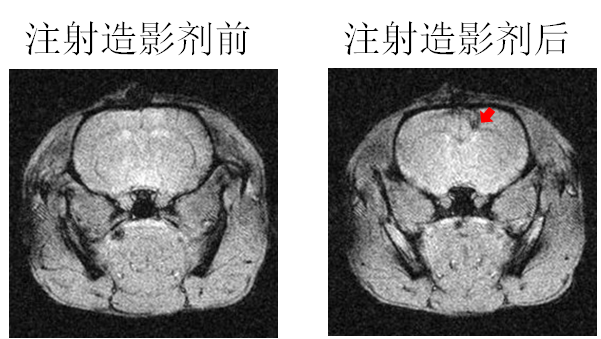

´ÅÐÔÄÉÃײÄÁÏ×÷Ϊ´Å¹²Õñ£¨MRI£©ÔìÓ°¼ÁµÄÓ¦ÓÃ